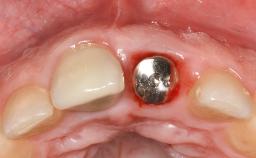

Treatment of Peri-Implant Mucositis at a Zirconia Implant

Recent clinical studies, most with short-to-medium term observation periods, have reported on the favorable clinical performance of zirconia implants in terms of survival rates, clinical, and radiographic outcomes (Roehling and coworkers 2016; Roehling and coworkers 2017; Rodriguez and coworkers 2018; Lorenz and coworkers 2019). Nonetheless, a rather high incidence of peri-implant disease at zirconia implants (39% of implants) was noted throughout a two-year period, highlighting the need for treatment protocols of peri-implant diseases at zirconia implants (Becker and coworkers 2017).